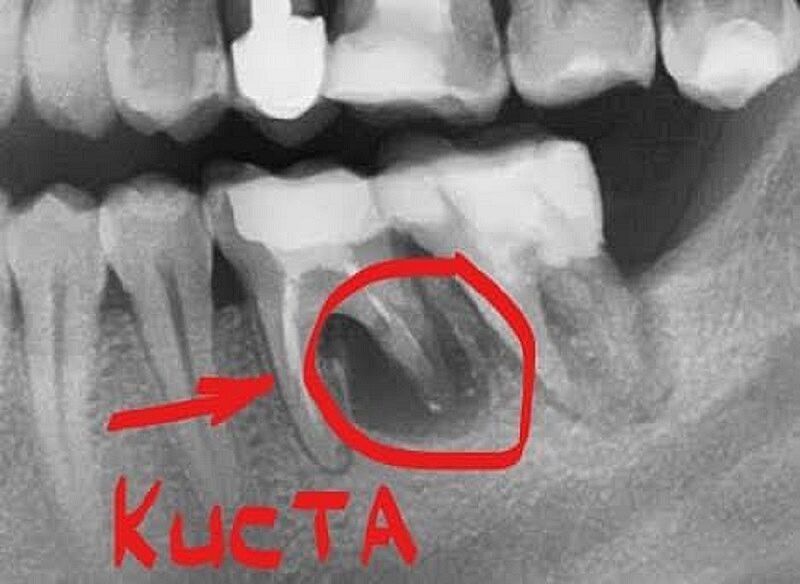

Киста зуба кто удалял

Начал периодически болеть зуб, пошла к врачу сделали снимок-киста. Чуть больше чем на фото, под корнем нижнего зуба жевательного. Врач сказал срочно ехать удалять зуб, что это очень опасно, тянуть нельзя. Проблема в том что кормлю грудью, ребенку 1,5 месяца.

Просто расстроена.. читаю здесь с кистой много лет ходят, а мне такую панику нагнали

а в идеале еще сделать КТ - там и с соседним нехорошо

Автор выложите здесь свой снимок

Добавила, может кто посмотрит и разбирается

Это снимок из интернета сейчас она добавила свой